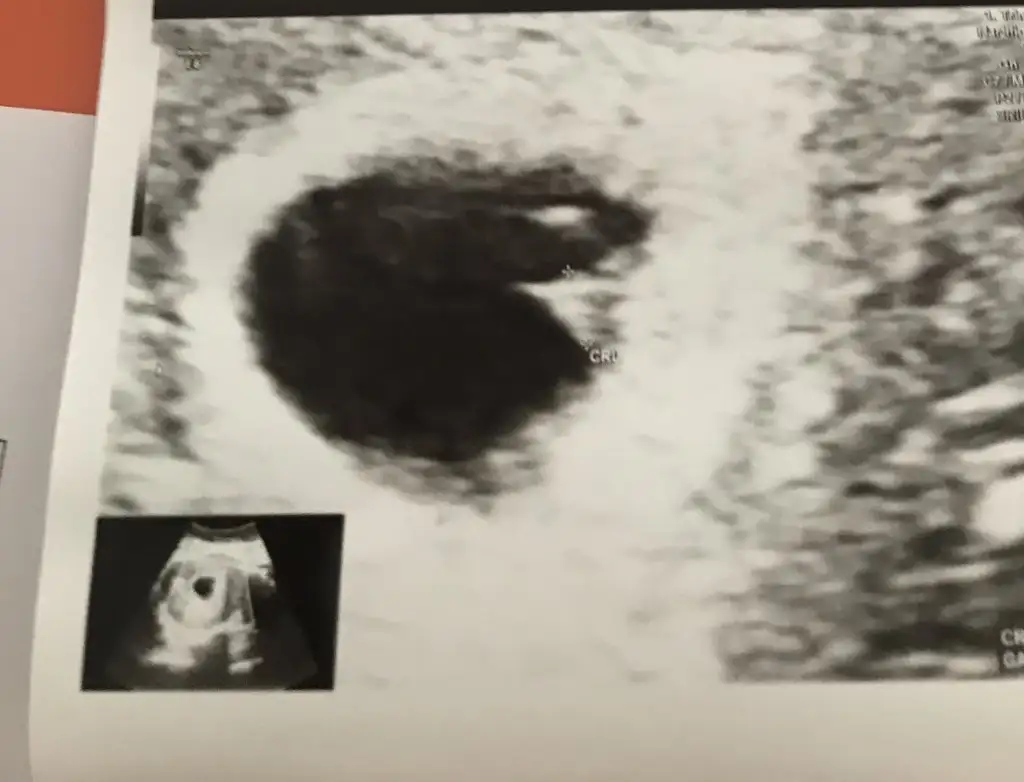

Bizim bebeğimiz içinde tahminde bulunur musunuz

Eklentiler

• 7 hafta.webp

47,3 KB · Görüntüleme: 91

• 5 hafta.webp

36,2 KB · Görüntüleme: 80